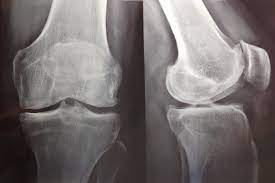

Hay evidencia de certeza alta de que el uso de antidepresivos para la artrosis de rodilla produce una mejoría insignificante desde el punto de vista clínico en el dolor medio y la funcionalidad. Sin embargo, un pequeño número de personas tendrá una mejoría importante del 50% o más en el dolor y la funcionalidad. Este hallazgo fue consistente en todos los ensayos. El dolor en la artrosis se podría deber a diversas causas que difieren entre las personas. Es posible que la causa del dolor que responde a este tratamiento solo esté presente en un pequeño número de personas. Hay evidencia de certeza moderada de que los antidepresivos tienen un pequeño efecto positivo sobre la calidad de vida, con heterogeneidad entre los ensayos. Cochrane Database of Systematic Reviews 21 de octubre de 2022